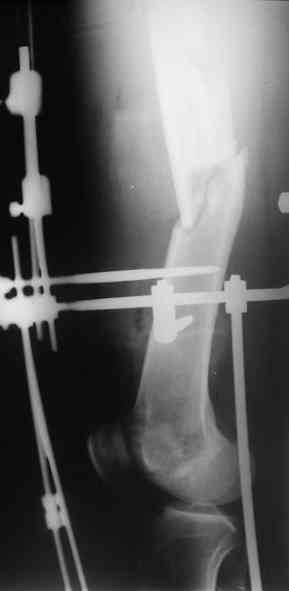

Лучше бы уточнить характер повреждения наружного мыщелка бедра, есть ли его фронтальное раскалывание. Мы бы сделали репозицию мыщелка (если получится, то закрыто) с фиксацией спонгиозными винтами.

Не получится закрыто - наружный парапателлярный доступ, открытая репозиция, винты. И сделали бы закрытый интрамедуллярный остеосинтез бедра антгерадно. Если есть возможность, лучше использовать гвоздь, который позволит провести винты через мыщелок, т.е. очень близко к

дистальному концу.

Вполне возможен и ретроградный остеосинтез бедра, особенно если все-таки придется открывать сустав.